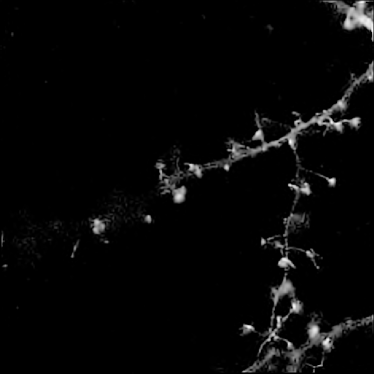

Finally, we applied our algorithm on a real confocal microscopy image of neurons. Fig. 4(a) depicts the observed image222Courtesy of the GIP Cycéron, Caen France. using the GFP fluorescent protein. Fig. 4(b) shows the restored image using our algorithm with the orthogonal wavelets. The images are shown in log-scale for visual purposes. We can notice that the background has been cleaned and some structures have reappeared. The spines are well restored and part of the dendritic tree is reconstructed, however some information can be lost (see tiny holes). This can be improved using more relevant transforms.

![]() |

| (a) | (b) |